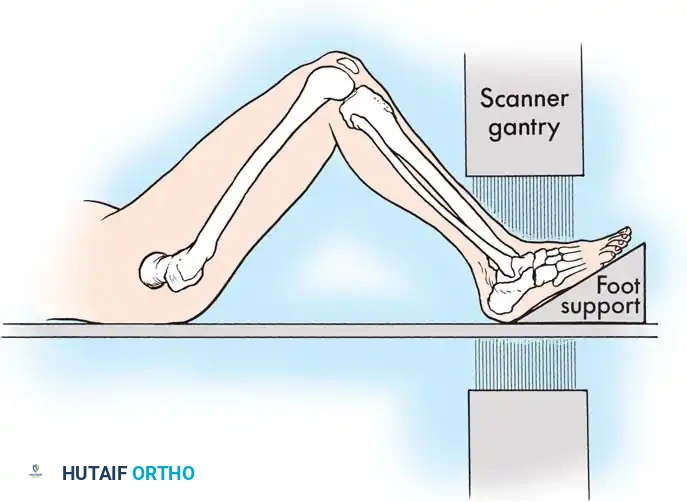

While plain films are essential, CT scanning is the gold standard for evaluating intraarticular calcaneal fractures. Scans must be ordered in two specific planes:

* Semicoronal Plane: Oriented perpendicular to the normal position of the posterior facet. This is the most critical view for assessing articular comminution and classifying the fracture.

* Axial Plane: Oriented parallel to the sole of the foot, excellent for evaluating the calcaneocuboid joint and the sustentaculum tali.

- Positioning: The patient is placed in the lateral decubitus position. A thigh tourniquet is applied.